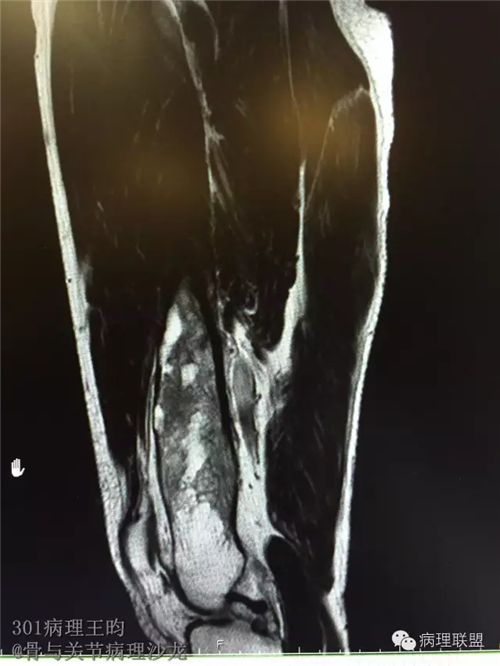

右股骨髓内高分化低级别骨肉瘤or骨纤维异常增殖症(Fibrous Dysplasia)?

男,36岁,活动后疼痛,发现右股骨远端肿瘤。